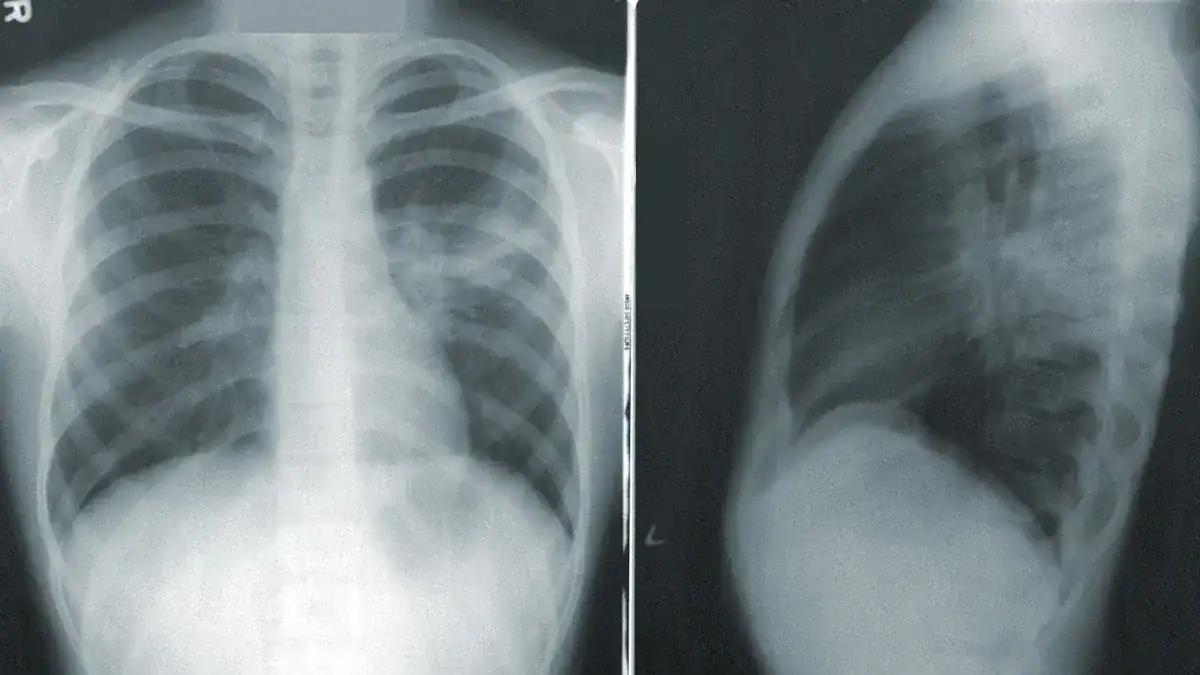

Imaging Tests

Imaging tests are crucial for seeing fluid in the lungs. They help confirm the diagnosis.

| Imaging Test | Sensitivity (%) | Specificity (%) |

|---|---|---|

| Point-of-Care Ultrasound (POCUS) | 83.6–100 | 70–100 |

| Chest X-ray (CXR) | 40–76.2 | 70–97 |

Lung ultrasound (LUS) and chest X-ray (CXR) are common imaging tools. LUS shows higher sensitivity and specificity than CXR for detecting fluid.